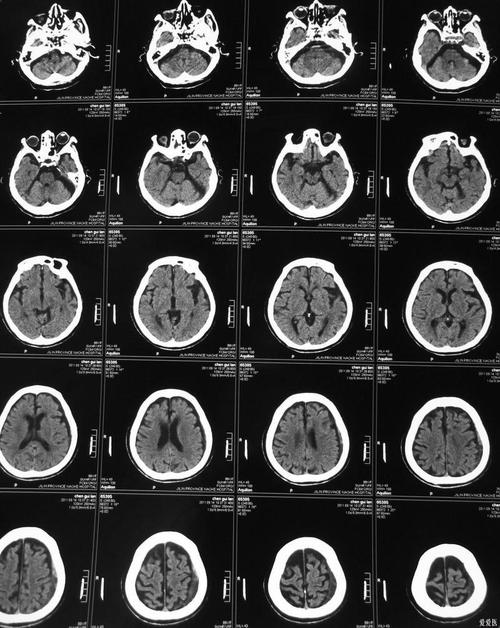

常规的、非增强的脑CT平扫,在脑梗发生的超早期(通常最初6小时内)检出率很低,难以明确诊断,但在发病后的特定时间点,它对诊断脑梗非常有价值。

脑梗死的本质是脑组织缺血、缺氧后坏死,CT影像上,坏死组织与正常脑组织在密度上会有差异,但这种差异的出现需要时间。

A. 超急性期(发病后6小时内)—— 检出率低

这是脑梗治疗的“黄金时间窗”,在这个阶段,由于脑细胞刚刚开始缺血坏死,细胞水肿刚开始,脑组织的密度变化非常微小,常规CT通常看不出明显异常。

B. 急性期(发病后6小时 - 3天)—— 检出率显著提高

随着缺血时间的延长,脑细胞坏死和水肿加重,坏死区域的脑组织密度会开始下降。

- 低密度灶: 在CT图像上,梗死区域会呈现为低密度(发黑)的阴影,这是因为坏死的脑组织水分含量增加,密度低于周围正常脑组织。

- 占位效应: 如果梗死面积较大,周围脑组织会发生明显水肿,导致脑室受压变形,中线结构移位。

在这个时间段,CT是诊断脑梗的重要和常用工具,能清晰显示梗死的位置、范围和严重程度。

C. 亚急性期(发病后4天 - 3周)—— 检出率最高

这个阶段是CT显示脑梗死最清晰的时期,脑水肿达到顶峰后开始消退,而坏死组织与正常组织的密度差异达到最大。

- 明显的低密度灶: 梗死灶边界变得非常清晰,呈均匀的低密度。

- “模糊效应”: 大约在发病后2-3周,坏死组织开始被吞噬细胞清除,密度可能暂时与正常脑组织相近,导致边界模糊,但这仍然是梗死的表现。

D. 慢性期(发病后3周以上)—— 仍可显示

- 脑软化灶: 坏死的脑组织最终被液性囊腔所取代,形成边界清晰的低密度区(脑脊液样密度)。

- 脑萎缩: 长期后,梗死区域会导致局部脑组织体积缩小,表现为脑沟加深、脑室扩大。